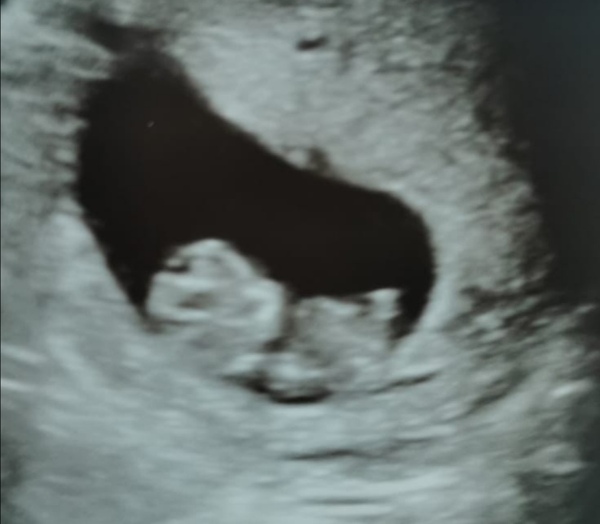

Hello, thank you so much for your kind supportive words guys, it honestly really means a lot! I actually saw a baby in there today inside me! I couldn't believe it! I was so shocked there were tears of relief! I'm 5 days behind what I thought but apparently that's normal, a nice little strong heartbeat too. I'm so in love!